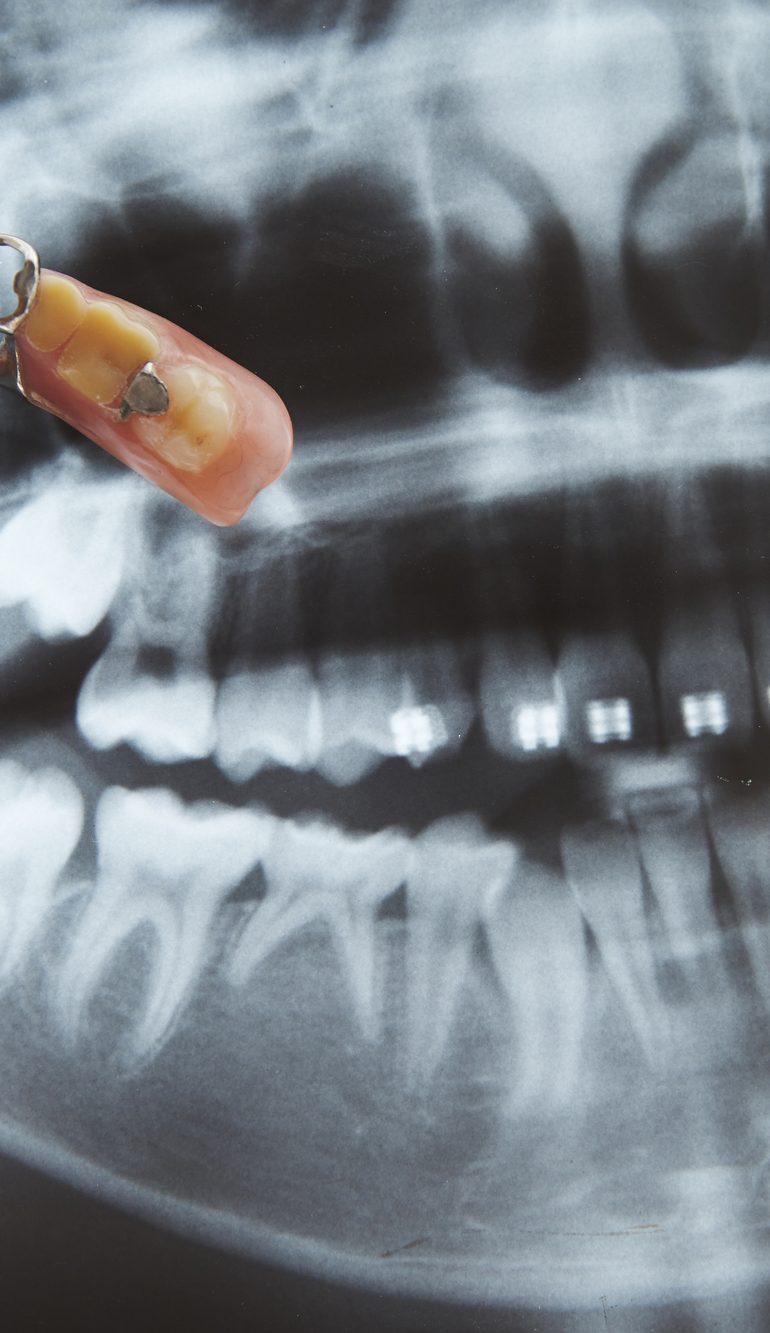

部分入れ歯とインプラントは、失った歯を補う治療方法として選択肢が異なります。

部分入れ歯は取り外し可能で、周囲の歯に負担をかけずに複数の歯を補える点が特徴です。

一方、インプラントは顎の骨に人工歯根を埋め込むため、固定式で見た目や咀嚼機能が自然な歯に近く、部分入れ歯よりも安定感があります。